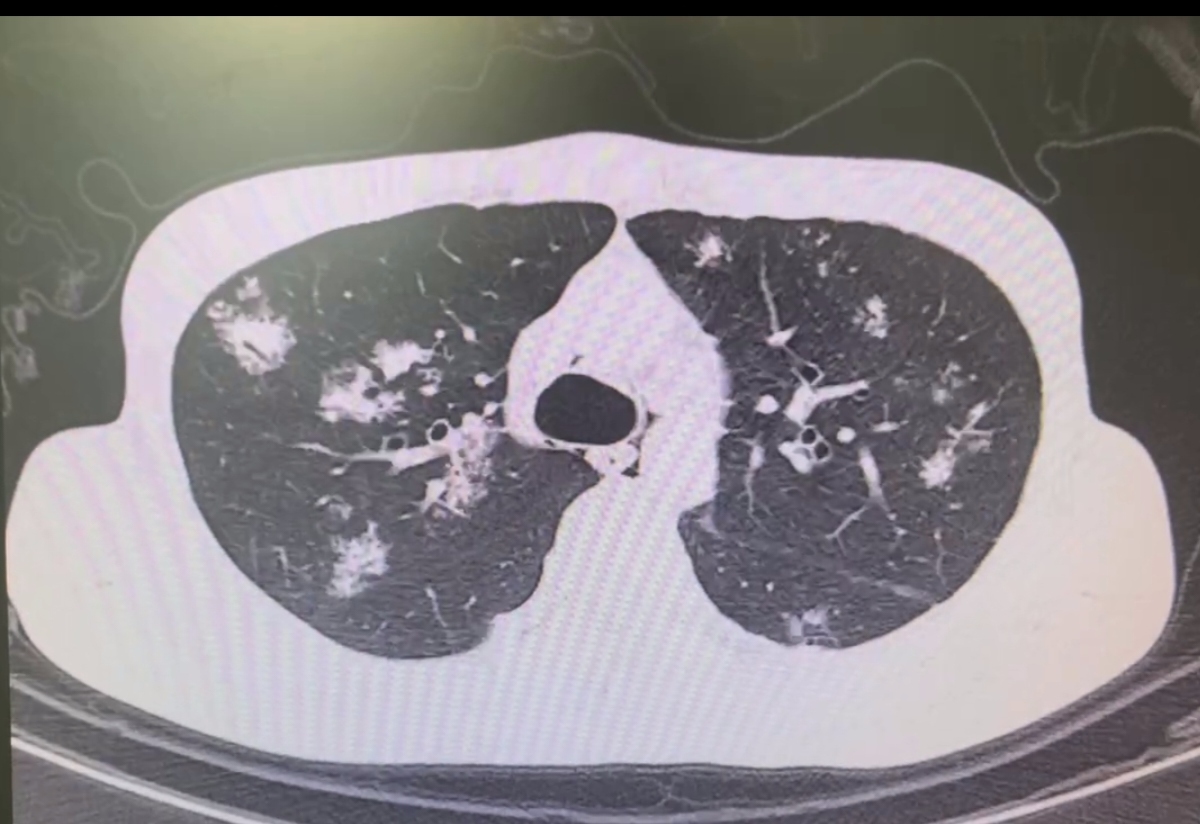

彌漫型結節:“肺城全域”的作亂小妖

彌漫型結節就像是散布在“肺城”各個區域的作亂小妖。

它們數量眾多、大小不一,如同《西游記》里那些嘍啰兵,遍布整個城市。這些小妖可不容忽視,彌漫型結節可能和塵肺病、肺部炎癥、轉移瘤之類的疾病有關。

它們就像在城市各個角落搗亂的嘍啰,讓“肺城”不得安寧,使得肺部的各個地方都可能出現問題。